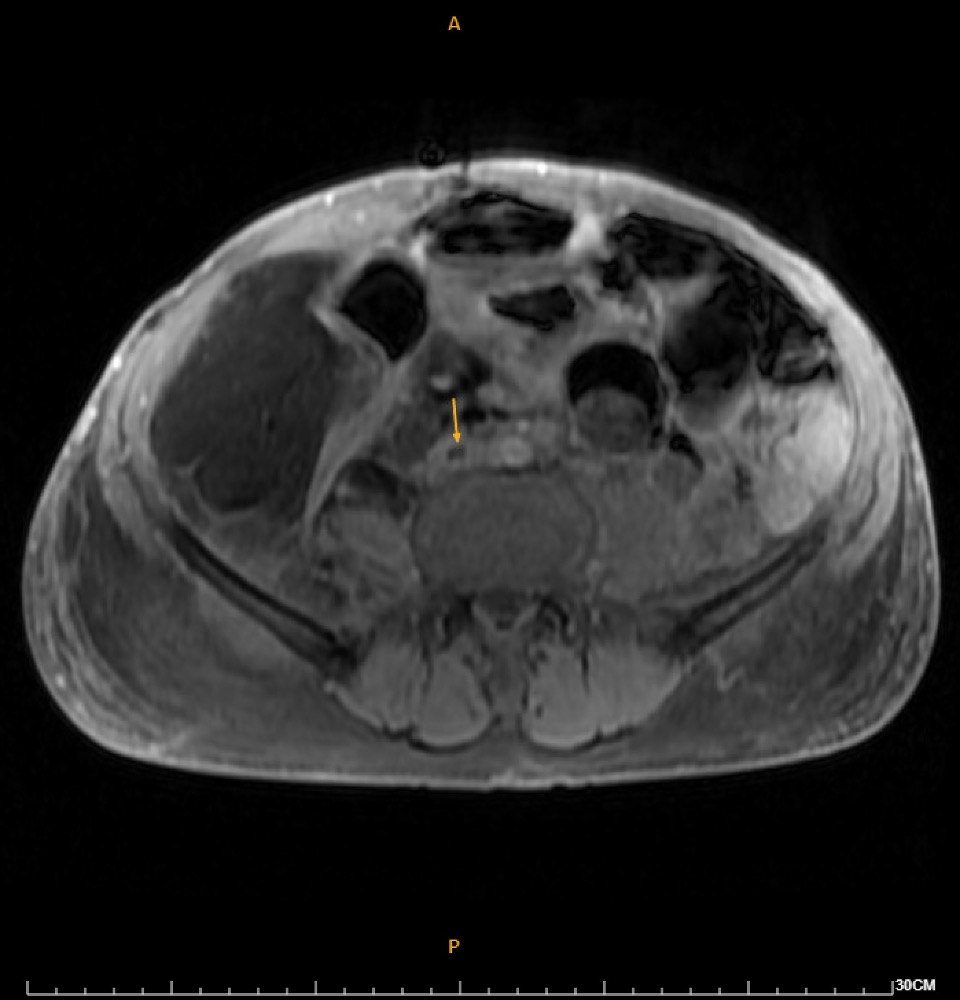

Duplex ultrasound demonstrated thrombosis from the right common femoral vein to the calf veins. MRI revealed a 16.8-cm retroperitoneal fat-containing tumor causing severe right hydronephrosis, and extensive thrombosis involving the right common, external, and internal iliac arteries, lower IVC, iliac, and femoral veins. DVT intervention was arranged.

Catheterization revealed total occlusion of the right common iliac artery, likely due to tumor compression. Diffuse thrombosis was seen in the right common femoral vein, with total occlusion from the right common iliac vein to proximal RCFV. LCIV ostial stenosis (~80%) and IVC stenosis (~90%) were also present.